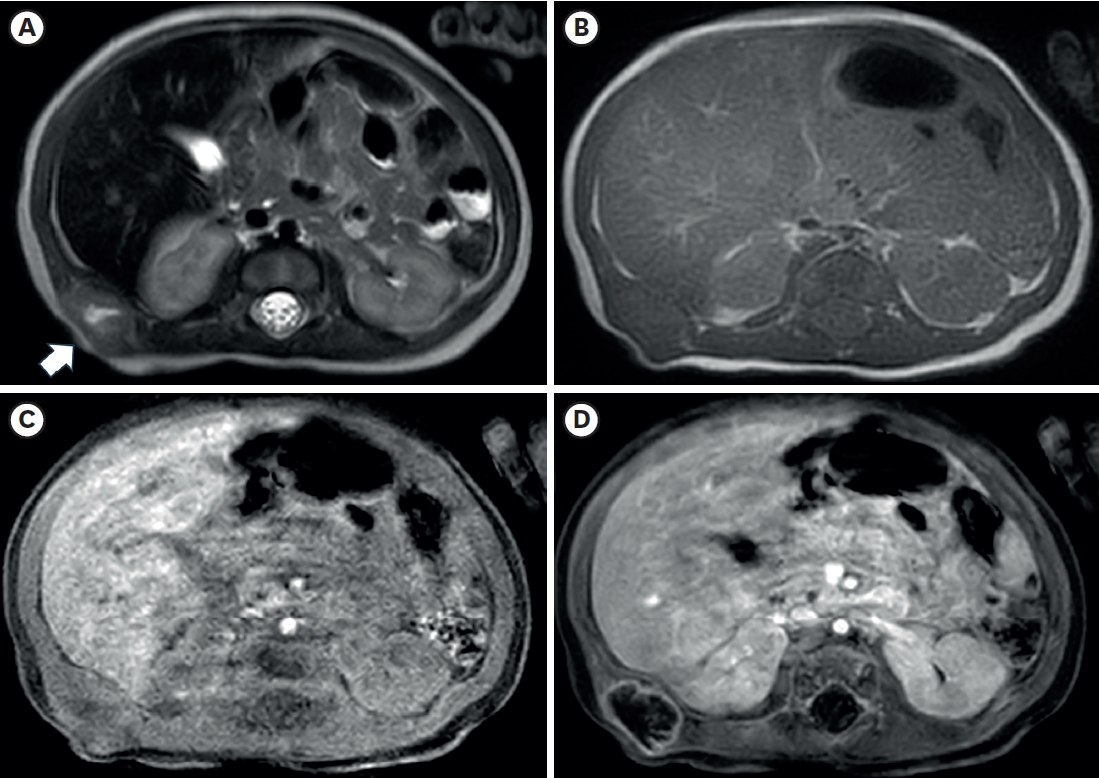

Fig. 2.Axial images of chest magnetic resonance imaging. (A) A lobulated soft tissue lesion (arrow) in the muscular layer of the body wall, just outside the right kidney and liver, with the internal cystic or necrotic portion on the T2-weighted image. The solid portion of the lesion shows (A) slightly high signal intensity compared with muscle on the T2-weighted image and (B) iso signal intensity on the T1-weighted image. T1-weighted axial images with fat suppression before (C) and after (D) contrast enhancement show only the lesion’s peripheral wall enhancement without filling the contrast material.

Fig. 1) showed a lobulated soft tissue lesion in the muscular layer, with an internal necrotic hypoechoic portion. Magnetic resonance imaging (MRI,

Fig. 2) also showed a lobulated mass with central necrosis, a well-defined margin, and peripheral rim enhancement in the muscular layer. The patient underwent surgical excision on the 20th day of birth for accurate diagnosis and treatment. In the operative findings, the mass was located in the latissimus dorsi muscle and butted to the right 12th rib, but dissection was performed without difficulties or injury to adjacent structures.

The radiologic findings of PM are also not specific [

11]. In this case, the preoperative US showed internal hypoechoic lesions, and the MRI also showed an internal hyperintense portion on the T2-weighted image, which suggested internal necrosis. These lesions were proven to be central degeneration without hemorrhage or necrosis. These findings have not been reported previously, and they could be one of the possible radiologic findings of PM.